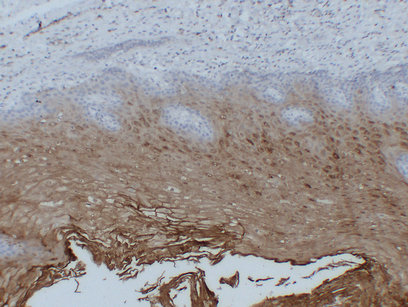

Immunohistochemistry analysis of paraffin-embedded Esophagus using Annexin A1 antibody.High-pressure and temperature Sodium Citrate pH 6.0 was used for antigen retrieval.